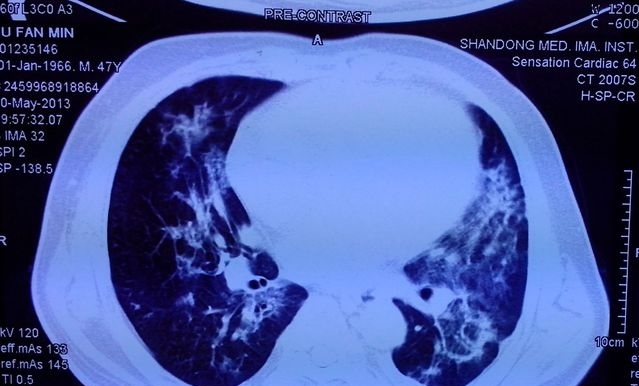

●在影像学上,尿毒症肺最典型的胸片则表现为“双侧肺野蝶翼状或蝙蝠状的渗出影”,说白了也就是以我们的肺门为中心,形成如蝶形或蝙蝠样阴影,如下图。我们大体上可将它的影像特点划分为5期,即肺泡性肺水肿期、肺淤血期、间质性肺水肿期、肺间质纤维化期和心脏扩大期。

尿毒症肺,影像中显著的渗出影

●但从个人经验来看,临床上还是以肺泡性水肿和心脏扩大期多见,因为这两种多会发生心衰,但这和普通的肺部感染是有着显著区别的,临床上如果能充分透析脱水这种蝶形或蝙蝠样渗出影可迅速消失,所以保证透析的充分性、增加超滤至关重要,也是这一并发症的核心治疗方案。